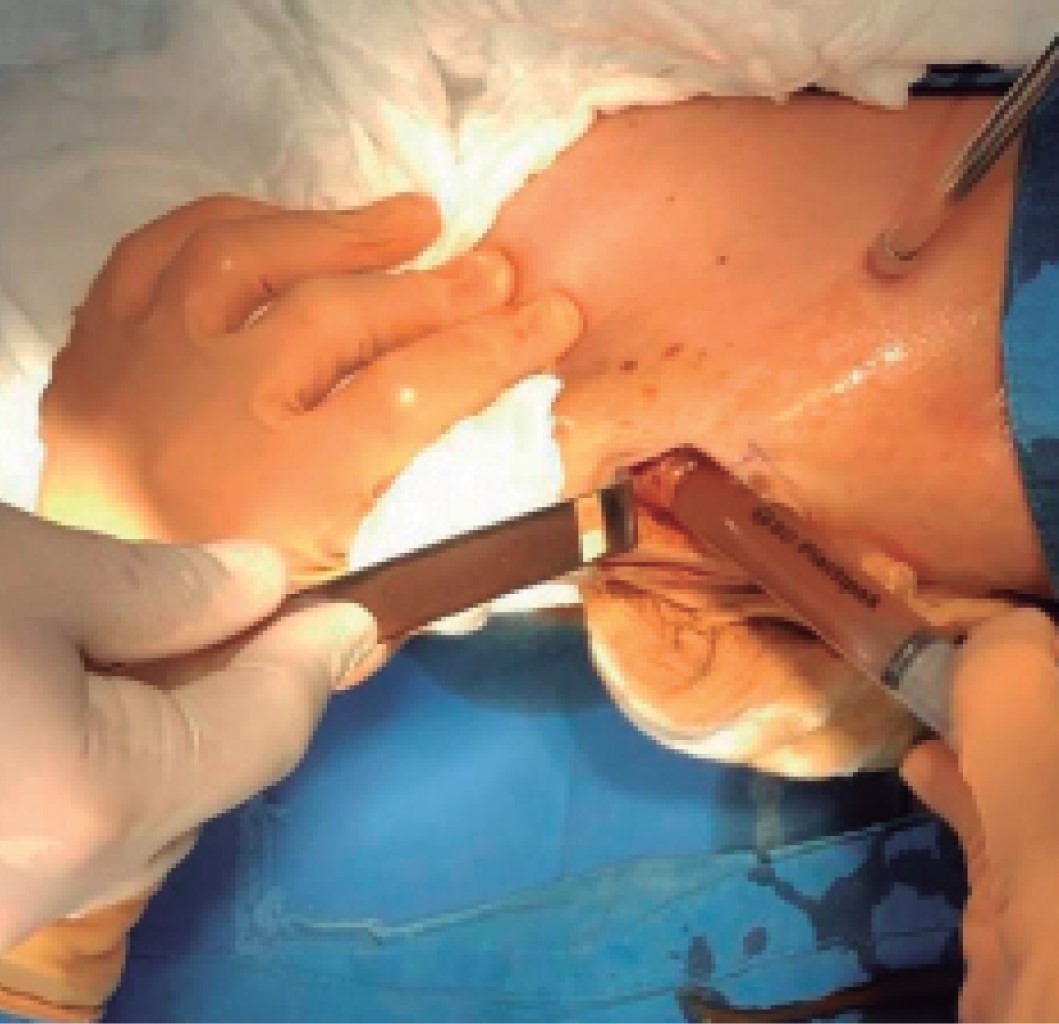

Procedimiento quirúrgico (Figuras 1, 2, 3, 4 y 5):

El 24 de octubre se llevó a cabo el retiro del implante de la pantorrilla izquierda bajo anestesia local y sedación. El retiro del implante derecho se difiere para otro tiempo quirúrgico (dos meses) a petición de la paciente para que se facilitara su movilidad en el postoperatorio. En la imagen preoperatoria observamos el aumento de volumen de la pierna izquierda (Figura 6).

Se realizó una incisión de 6 cm por debajo del hueco poplíteo, se disecaron los tejidos hasta identificar la cápsula del implante; al incidirla drenó aproximadamente 350 mL de líquido oscuro (achocolatado), inodoro. Se procedió a la extracción del implante, se encontró con varias perforaciones por donde se fugaba el gel de silicón y se resecó la cápsula (Figuras 7, 8 y 9). En seguida se efectuó un aseo del bolsillo con solución fisiológica y agua oxigenada, se colocó un drenaje de silicón y se suturaron las heridas en dos planos: el tejido celular subcutáneo con vicryl 4-0 y la piel con nylon 4-0, para finalmente cubrirse con gasa y vendaje. El líquido y la cápsula fueron enviados a patología y laboratorio para su cultivo. Se manejó como paciente externa y se le prescribió ketorolaco, cefalosporina y etamsilato. Al cuarto día se le retiró el drenaje por haber drenado sólo 5 mL en 24 horas y color serohemático. Al décimo día se retiraron los puntos y se indicaron medias elásticas y deambulación.